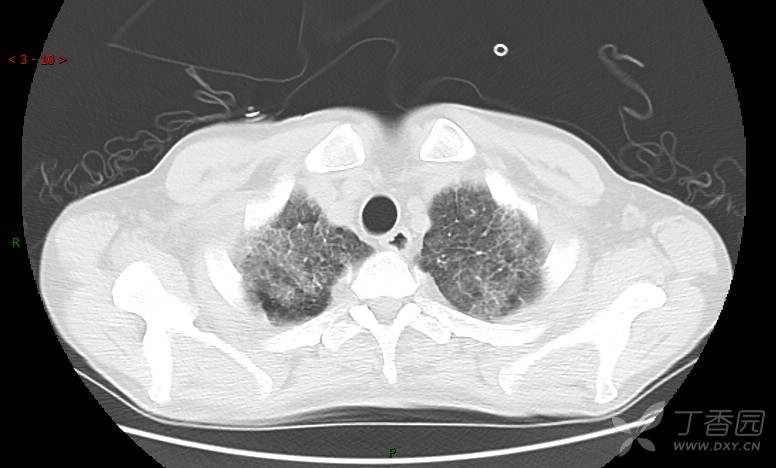

患者男,42岁,咳嗽半年余,加重伴憋喘2月余。

患者半年余前无明显诱因出现间断咳嗽,干咳为主,偶咳少量黄白痰,剧烈咳嗽或运动后可出现轻度憋喘,无高热、脓臭痰,无胸痛、咯血及晕厥,无低热乏力及盗汗,无心前区压榨感及夜间阵发性呼吸困难,初未在意,未予正规诊治。2月余前患者自觉上述症状较前加重,咳嗽、憋喘明显,黄白色粘痰略有增多,伴有发热,热前伴有畏寒、寒战,体温最高达38.9℃,先后就诊多家医院,入住重症监护室,未行气管插管,考虑“重症肺炎”,给予“美罗培南、复方磺胺甲噁唑”等药物抗感染,“卡泊芬净”抗真菌,并给予“甲泼尼龙”等药物治疗35天,经治疗后症状好转于2018-04-02出院。患者自出院后仅应用中药治疗(具体不详),并给予家庭氧疗,平素仍有间断咳嗽,咳少量黄白色粘痰,活动后憋喘明显,活动耐量差,以卧床为主。

肺内弥漫性网状结节影,PET-CT却无阳性病灶,这是?(附其他2例链接)